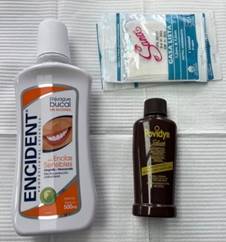

Se realiza la asepsia extraoral del paciente con Yodo Povidona (Povidyn) la cual se aplicó con una pinza hemostática con una gasa, e intraoral con Clorhexidina al 0.12% la misma que el paciente mantuvo en su boca durante 30 segundos. (Figura 2).

Figura 2. Técnica de asepsia.

Elaboración: Los autores.